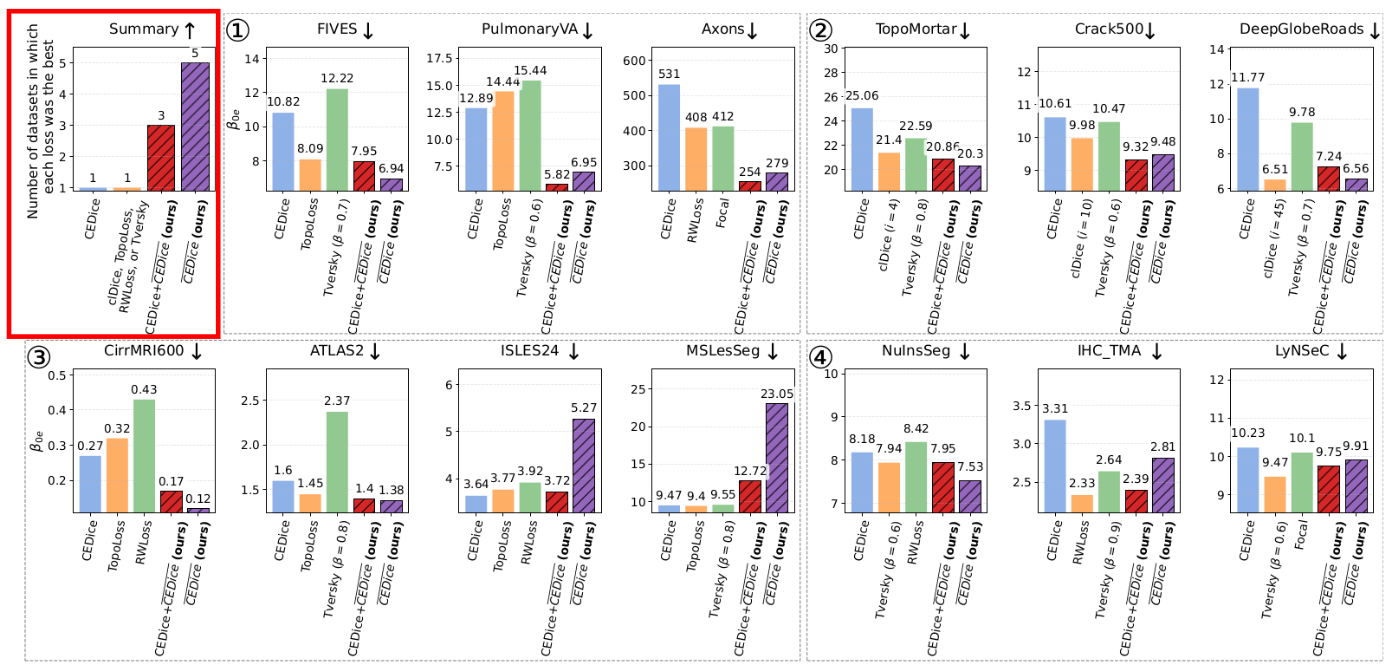

We conducted 1) a benchmark across 13 datasets comparing 5-7 loss functions vs. Cross Entropy Dice loss with our SCNP; 2) a sensitivity analysis on SCNP's only hyper-parameter (neighborhood size); and 3) an ablation study comparing nine loss functions with and without SCNP. Each experiment was run with five different random seeds. In the benchmark, we employed medical and non-medical datasets, datasets with tubular and non-tubular structures, semantic and instance, binary and multi-class segmentation tasks, and three state-of-the-art DL frameworks (nnUNetv2, Detectron2, InstanSeg).

SCNP improved topology accuracy without deteriorating Dice coefficient.

Our sensitivity analysis indicates that the optimal neighborhood size of SCNP is correlated with the structure size.